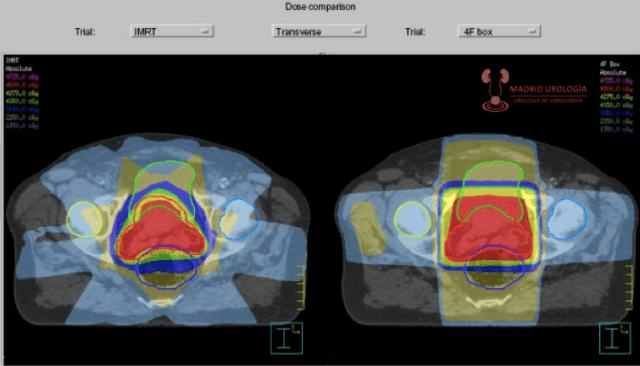

RADIOTERAPIA PREQUIRURGICA

Teóricamente la administración de radioterapia preoperatoria permitiría tener células tumorales menos viables durante la manipulación quirúrgica posibilitando la reducción de márgenes quirúrgicos con la posible disminución de la recidiva local.